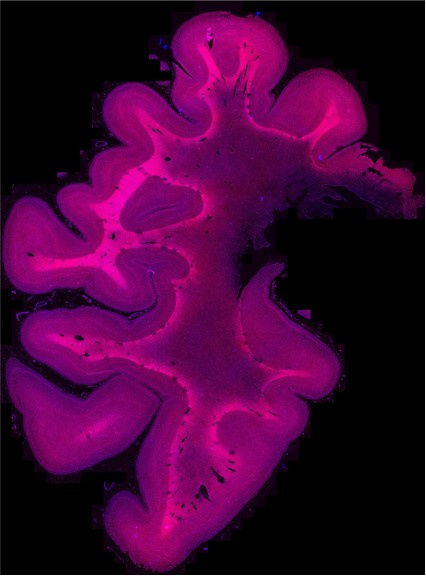

Human brain mapping

MRI histology mapping